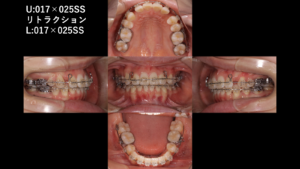

・埋伏犬歯の外科的処置・乳歯の抜去・下顎小臼歯の抜歯・上下ワイヤー矯正

本症例では、埋伏している犬歯を摘出したため前に投稿したブログと同じように、戦略的に第1小臼歯(4番)を犬歯の代わりとして活用しています。また患者さんの4番は形態的にも犬歯に近く、適切にコントロールすることで、見た目の自然さと機能の安定性を両立することが可能です。

また、ブラケット位置はかなり迷いましたが、3番と同じ部位に付けることとしました。

前歯の突出感が改善し、歯列全体のバランスが整いました。また、それにより、咬合が安定しています。

治療期間:2年3ヶ月

費用:99万円(税込